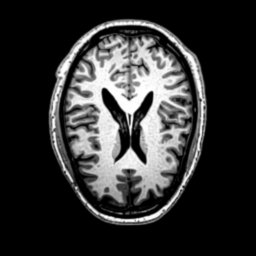

We use the Pix2Pix Zero model with a basic fine-tuned Stable Diffusion model to generate healthy brain MRIs from ones diagnosed with Alzheimer’s Disease and vice versa. We generate the counterfactual images by negating the ground truth label of the 200 test samples and conditioning the model on the negated label value and the source image. We compute image quality metrics, as well as the AUC, using a disease classification model trained on 600 real brain MRI slices (300 AD, 300 CN). Additionally, we determine the Structure Similarity Inced (SSIM) between the target and the source image to determine how well the identity of the source image is retained. The qualitative results in Fig. 6 , illustrate four examples from our two editing directions: from AD to CN and from CN to AD, respectively. When transitioning from AD to CN, the model primarily reduces the size of the ventricles. Conversely, in the CN to AD transformation, the ventricle size increases, accompanied by a worsening of brain atrophy.